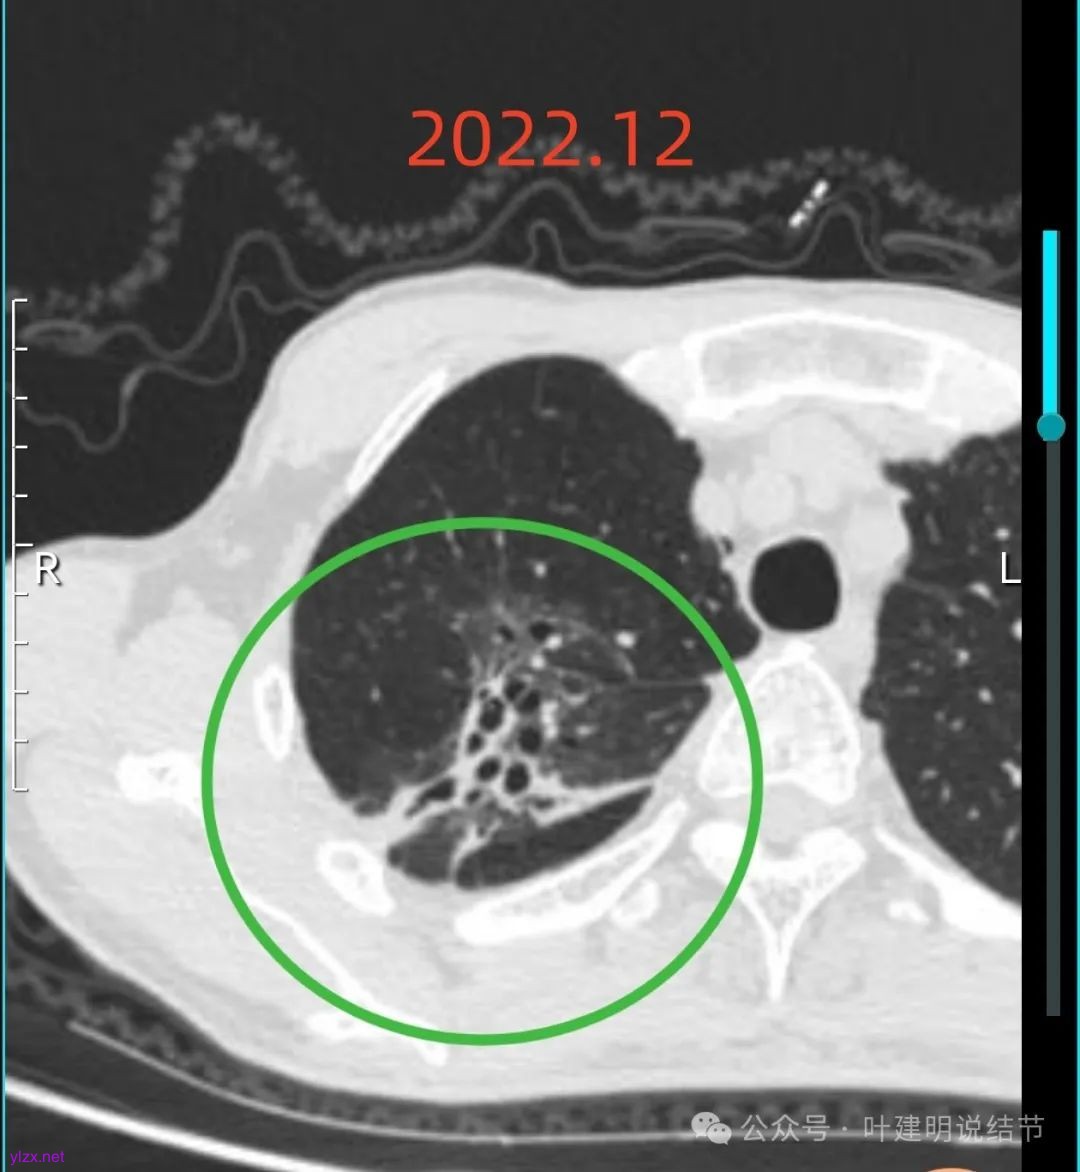

我们先来看2022年12月时的影像:

右上叶蜂窝状混合密度阴影,有较多磨玻璃成分,灶内有支气管扩张,邻近胸膜有增厚,总体感觉更像支气管扩张伴慢性炎及纤维增生,但有时肿瘤性病变也会类似,还需要随访对比才能更有倾向性。